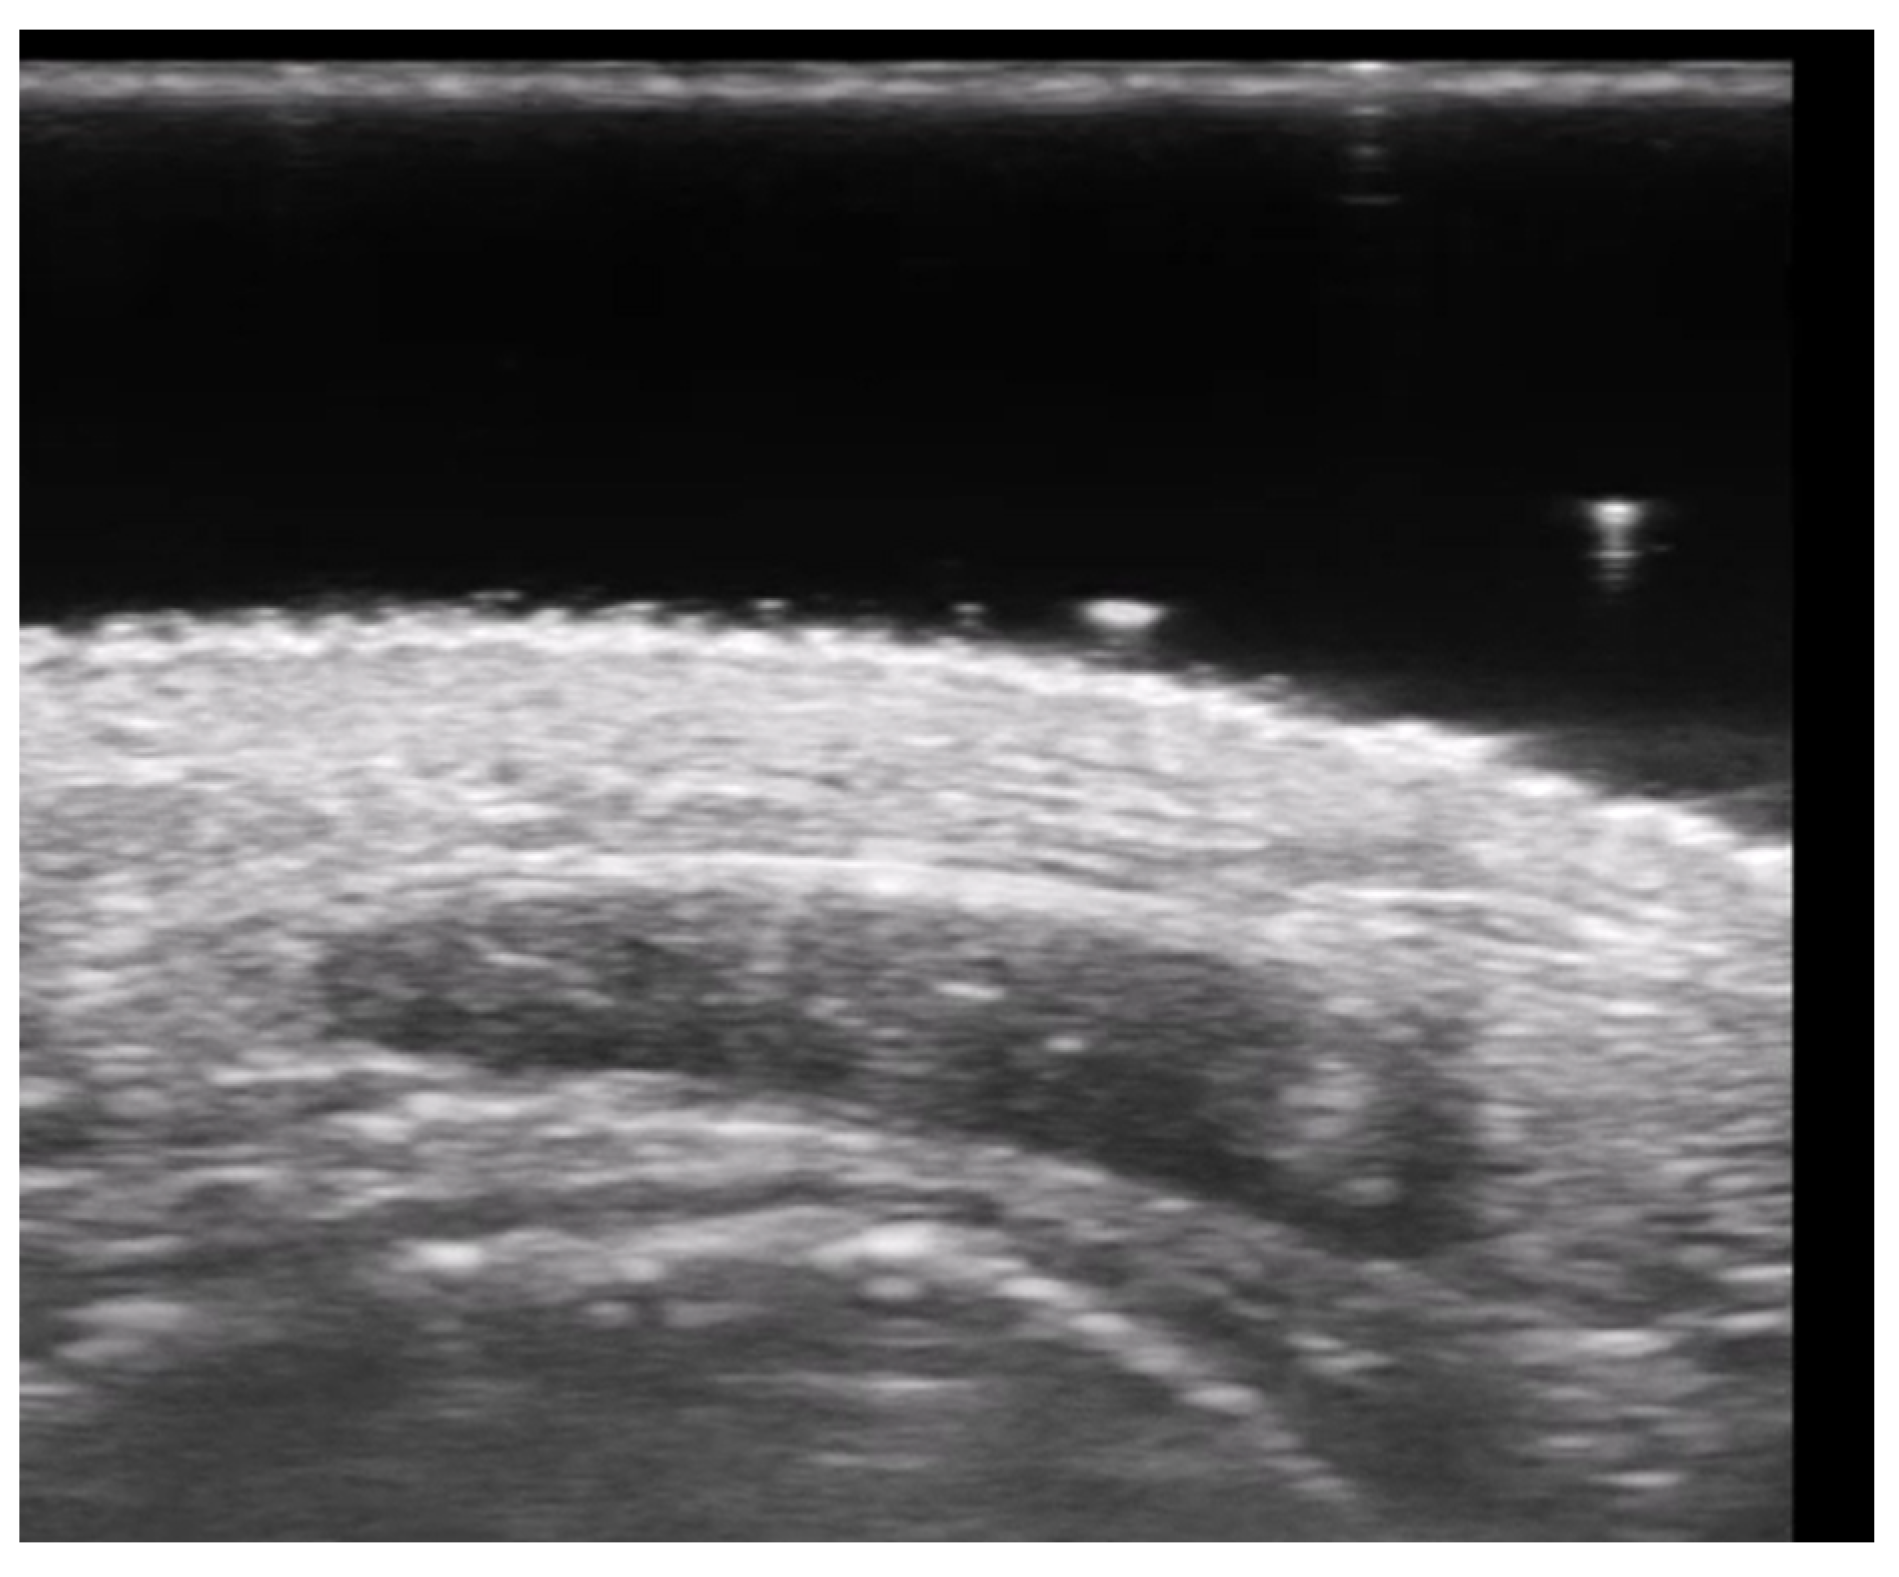

4. Metabolic and Genetic Disorders